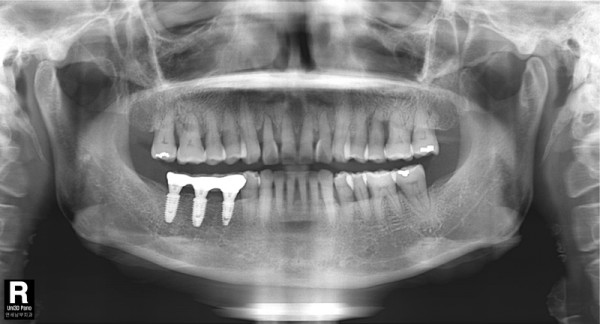

60대 남, 임플란트